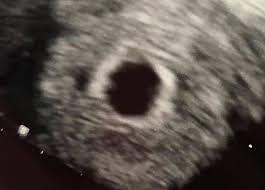

Ultraschall schwangerschaft 6. woche. Schwangerschaft - 6. Eindeutig erkennbar ist das pulsierende Herz aber meistens erst in zwei bis drei Wochen. Schwangerschaftswoche 8 0 bis 11 6 SSW 1Screening 18 0 bis 21 6 SSW 2Screening 28 0 bis 31 6 SSW 3Screening.

Schwangerschaftswoche sind auch die Struktur des Embryos und sein Herzschlag zu erkennen. Eine frühe Ultraschalluntersuchung dient vor allem dazu die Schwangerschaft zu bestätigen und eine Eileiterschwangerschaft auszuschließen. Die Entwicklung des Embryos schreitet nun rasant voran.

SSW Details zu Entwicklung des Babys der erste Ultraschall Schwangerschaftssymptome Tipps zur Linderung uvm. Vom Bauch des Embryos aus führt die Nabelschnur in der sich nun Blutgefäße zum Transport der Nährstoffe bilden zur Plazenta. Ist Dein Gynäkologe mit entsprechender Technik ausgestattet kann er die Schwangerschaft in der 6.

Woche SSW 5 If playback doesnt begin shortly try restarting your device. Schwangerschaftswoche deinen ersten Ultraschall-Termin hast wirst du wahrscheinlich die Fruchthöhle und den Dottersack sehen können. Auf dem Ultraschall in der 6. Eine Ultraschalluntersuchung vor der vollendeten 6. Das ist jedoch erst mal kein Grund zur Beunruhigung. Wie geht es dir und dem Baby. Ultraschall nichts zu sehen ssw 66. Hier kann man auch feststellen ob das Baby in der Gebärmutter eingenistet ist und der Arzt kann die Schwangerschaft bestätigen. In der Regel werden Zwillinge bereits bei der ersten Ultraschalluntersuchung entdeckt die etwa in der sechsten Schwangerschaftswoche erfolgt Sie sind 5 Wochen schwanger SSW 5 oder in der 6.

Ist Dein Gynäkologe mit entsprechender Technik ausgestattet kann er die Schwangerschaft in der 6. Ab etwa der 6. Schwangerschaftswoche Zwillinge in SSW 5. SSW Details zu Entwicklung des Babys der erste Ultraschall Schwangerschaftssymptome Tipps zur Linderung uvm. Schwangerschaftswoche passiert viel mit deinem Körper und deinem Baby. Schwangerschaftswoche sind auch die Struktur des Embryos und sein Herzschlag zu erkennen. Schwangerschaftswoche einen Termin beim Frauenarzt haben kann es sein dass im Ultraschall noch nichts zu sehen ist.